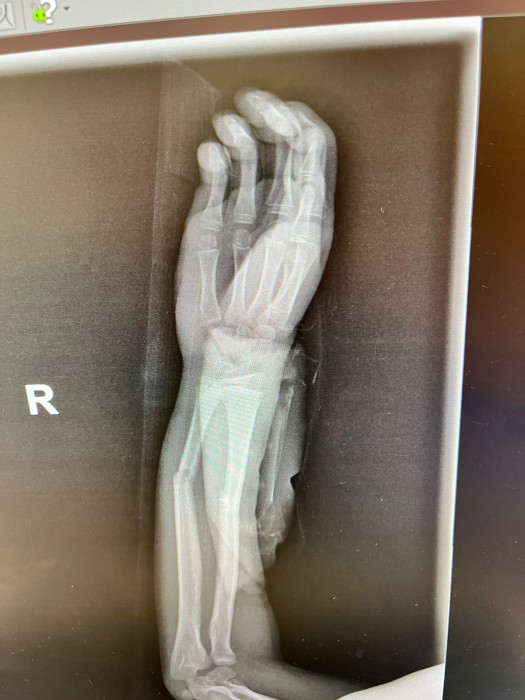

Кораблёв С.Г.: Да, вот ребёнок, 8 лет. Видно, перелом двух костей предплечья.

Кораблёв С.Г.: Адам, ещё раз: это второй снимок — боковая проекция. Это он на гипсе, это первичная репозиция, соответственно. И, вот, буквально они сделали на днях снимки, и всё прекрасно. Доктора сами удивились.

Кораблёв С.Г.: Да, так вот на кушетке, рука - я гипс снимал, и водил чашу по руке.

Кораблёв С.Г.: Я забыл сказать, что немного неправильно выбрали тип операции. Соответственно, здесь они поставили спицы, видите, но полностью сопостава не было. И там была еще ошибка, видимо, студенты удаляли, и после этого резко дёрнули, и перелом съехал в это положение. Это после операции. Они сказали: «Давайте подождем». И вот их выписали. Я смог забрать пациента себе, и вел на реабилитацию, поменял гипс, стянул, и мы каждый день работали-работали. И потом я с вашим методом познакомился.